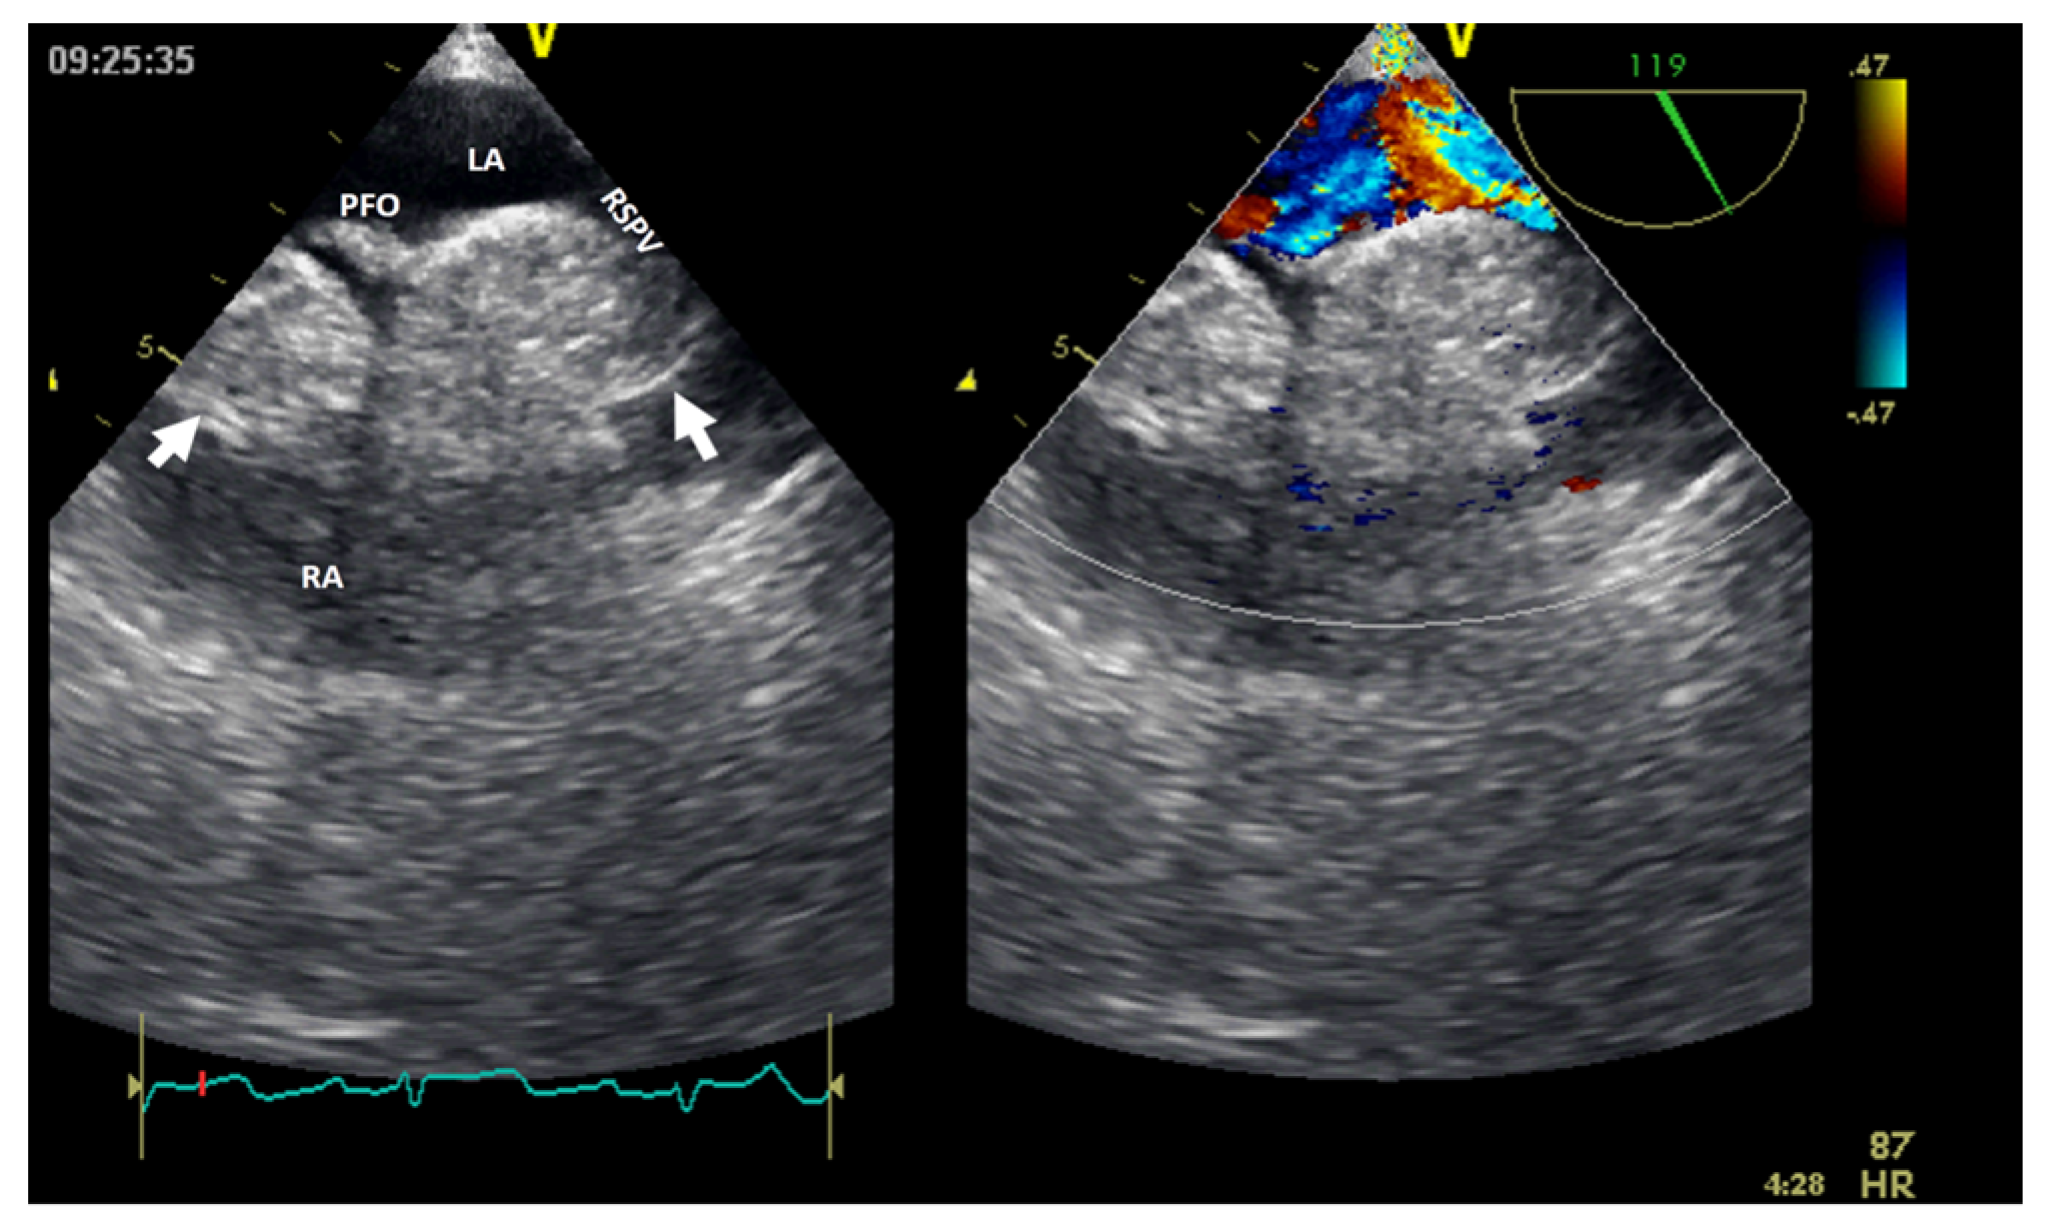

- Floria, M.; Guedes, A.; Buche, M.; Deperon, R.; Marchandise, B. A rare primary cardiac tumour: Cavernous hemangioma of the tricuspid valve. Eur. J. Echocardiogr. J. Work. Group Echocardiogr. Eur. Soc. Cardiol. 2011, 12, 477. [Google Scholar] [CrossRef] [PubMed][Green Version]